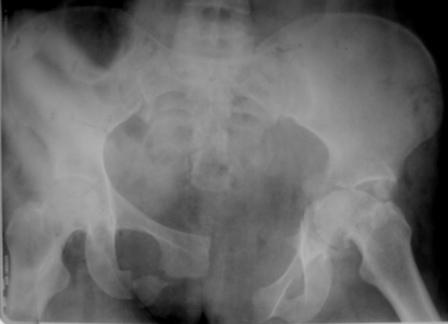

Застарелое повреждение таза

Уважаемые коллеги! Пациентка 32 года с застарелым повреждением таза, после остеосинеза лонного сочленения пластиной. Посоветуйте с выбором тактики и методик лечения.

Получила травму в феврале 2004г в г.Лобытнанги ЯНАО Тюм.обл. Через неделю после поступления выполнен остеосинтез лонного сочленения пластиной. 1,5 месяца на скелетном вытяжении. В последующем ходит при помощи костылей с нагрузкой на правую ногу. Имеется нестабильность половин таза, неправильно-консолидированный перелом левой вертлужной впадины, невропатия седалищного нерва слева. В результате невропатии седалищного нерва сформировалась эквинусная установка левой стопы, парестезии по подошвенной поверхности.

Направлена к нам для устранения патологической установки стопы и эндопротезирования левого тазобедренного сустава, также имеется миграция шурупов пластины, фиксирующей лонное сочленение.

Клинически: ходит на костылях с нагрузкой на правую ногу. Левая стопа в эквинусе. Осевая нагрузка на левую н\конечность болезненна в области левого тазобедренного сустава, при прикосновениях к подошвенной поверхности стопы у пациентки чувство зжения. В левом коленном суставе полный обьем движений, в левом тазобедренном резко ограничено отведение и ротация, укорочение левой н\конечности на 2,5 см. При полипроекционной и функциональной Р-графии выявлена нестабильность левого КПС и лонного сочленения, консолидированный в порочном положении поперечный оскольчатый перелом левой вертлужной впадины с центральным смещением головки бедра. Нами выполнена коррекция деформации левой стопы. Планируется выполнить введение 2 канюлированных илиосакральных винтов слева, реостеосинтез лонного сочленения реконструктивной пластиной, после заживления ран - тотальное эндопротезирование левого тазобедренного сустава.